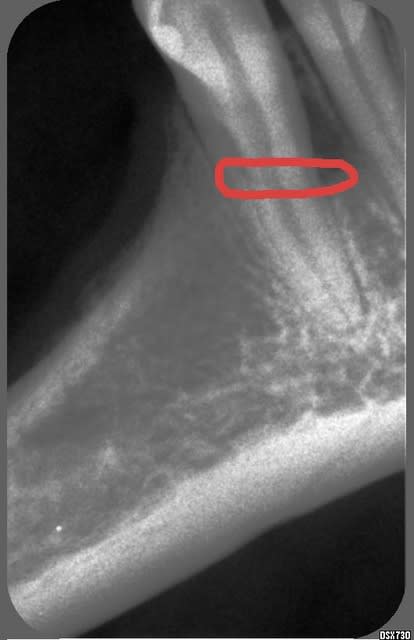

02/12/2004 à 20h37

Une un peu plus claire

Enigme2 edbyto - Eugenol

Es-tu sûr que ce n'est pas la limite supérieure de l'os alvéolaire en lingual?